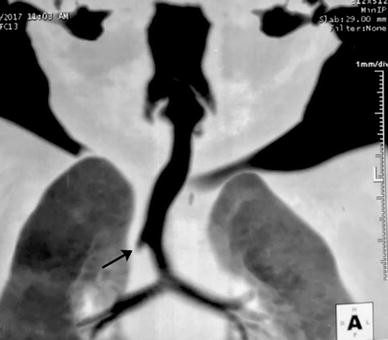

The following day, the child underwent helical computed tomography (CT) bronchoscopy using helical datasets from the base of the skull to T4 on a 64-detector scanner (Terrarecon workstation; Aquillion 64, Toshiba America Medical Systems, Tochigi, Japan). The CT scan revealed the presence of an accessory (i.e., tracheal) bronchus arising from the right posterolateral wall of the trachea (Figure). We suspected that the distal end of the ETT abutting on the tracheal bronchus resulted in the inability to ventilate and resistance to advancing the ETT. The child was subsequently successfully anesthetized and intubated using a 4-mm ETT that was advanced with its tip rotated at 180° to avoid being diverted into the accessory bronchus. A flexible bronchoscope had been prepared to facilitate ETT passage had our initial attempt been unsuccessful.

Computed tomography shows a typical presentation of the tracheal bronchus (arrow) originating from the right posterolateral position approximately 2 cm above the carina.